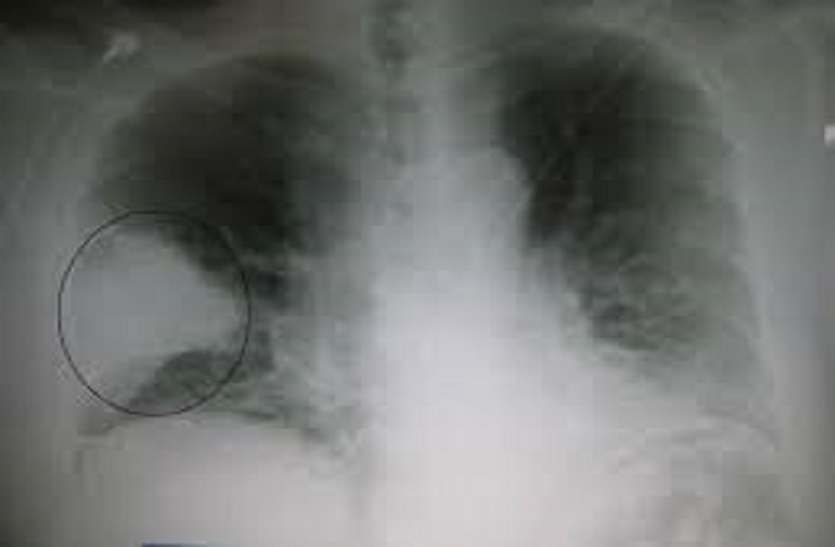

आरसीएचओ डॉ. अमर सिह सैनी ने बताया कि निमोनिया फेफड़ों में होने वाला संक्रमण है, जो कि बच्चों में सर्वाधिक होने वाला संक्रमण है। सांस कार्यक्रम के तहत प्रत्येक स्तर के अधिकारी एवं स्वास्थ्य कार्यकर्ताओं का प्रशिक्षण आयोजित किया जा रहा है। इसके साथ ही एएनएम एवं आशा सहयोगिनी स्तर पर आवश्यक प्रशिक्षण एवं दवा दी गई है। समुदाय स्तर पर निमोनिया के लक्षण, बचाव व रोकथाम के लिए चिकित्सक व स्टाफ नर्स को प्रशिक्षण दिया जा रहा है। ताकि वह समुदाय में जाग्रति पैदा कर निमोनिया के बचाव हेतु आमजन को प्रेरित कर सकेंगे। वही राज्य स्तर के निर्देशानुसार सांस कार्यक्रम का व्यापक प्रचार-प्रसार किया जा रहा है। इसके तहत विभिन्न प्रकार की आईईसी गतिविधियां संपादित कर आमजन को जागरूक किया जा रहा है।

निमोनिया फेंफड़ों में रोगाणुओं के संक्रमण से होता है और पांच वर्ष तक के बच्चों में इसका खतरा अधिक रहता है इसमें खांसी और जुकाम का बढऩा, तेजी से सांस लेना, सांस लेते समय पसली चलना, तेज बुखार आना के साथ झटके आना, खाना-पीना पाना एवं सुस्ती या अत्यधिक नींद आना मुख्य है। ऐसे समय मे बच्चों की विशेष देखभाल की जाए।